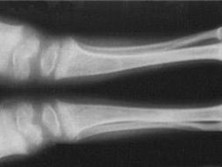

新生儿佝偻病(ricketsofnewborn)因为维生素D钙(或)钙磷缺乏引起...

X线平片